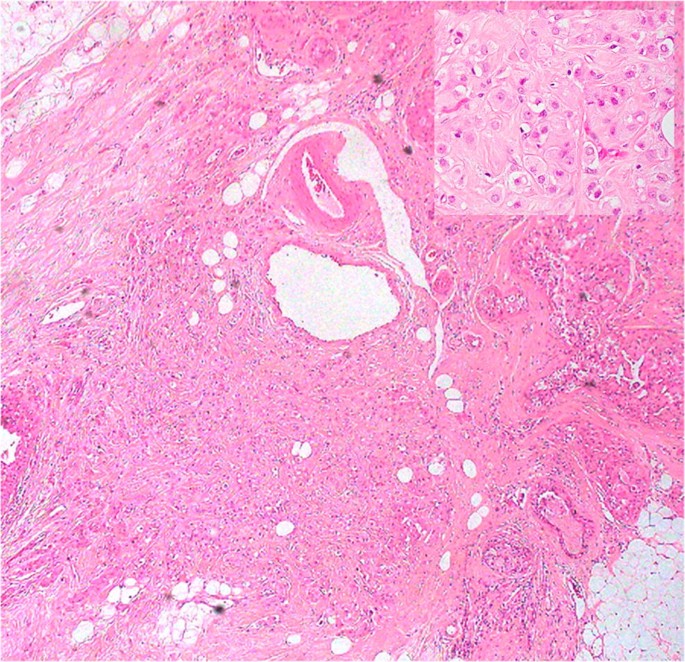

Fig. 2

figure 2

On histology, all the tumors showed the typical CAD features, being composed of eosinophilic cells. Inset: at higher power, the neoplastic cells show eosinophilic and granular cytoplasm, atypical nucleus and prominent nucleolus